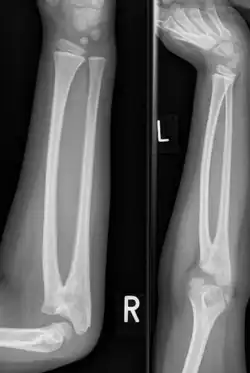

| Congenital radioulnar synostosis in a 7-year-old boy | |

Radioulnar synostosis is a rare condition where there is an abnormal connection (synostosis) between the radius and ulna bones of the forearm.[1] This can be present at birth (congenital), when it is a result of a failure of the bones to form separately, or following an injury (post-traumatic).[2]

It typically causes restricted movement of the forearm, in particular rotation (pronation and supination), though is usually not painful unless it causes subluxation of the radial head.[1] It can be associated with dislocation of the radial head which leads to limited elbow extension.[2]